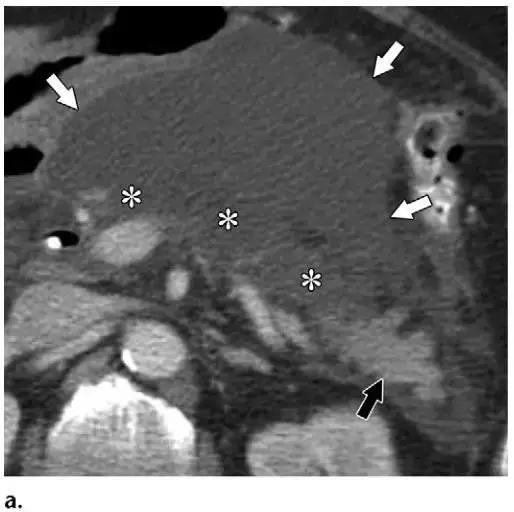

同时受累的亚型:表现为胰腺及胰周无强化坏死物,多累及小网膜囊和肾前间隙(图 3a)。

胰周型:表现为胰腺强化正常,而胰周坏死,坏死物可包括不等量的液体和和非液性成分,约占坏死性胰腺炎的 20%(图 3b)。

图 3 坏死性胰腺炎亚型在增强轴位 CT 的表现。a 胰腺和胰周同时受累的 58 岁女性患者,胰体无强化(*),正常强化的胰尾(黑箭头),小网膜囊内 ANC(白箭头)。b 仅胰周受累的 18 岁男性患者,可见一周为大片不均质密度(箭头),和 ANC 相符。胰腺实质密度正常(*)。c 仅胰腺实质受累的 33 岁男性患者,可见大片局限无强化的胰腺实质和脂肪密度(*),诊断为 WON。仅周边可见少量残余强化的胰腺实质(箭头)